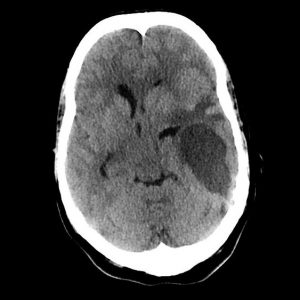

Xuất huyết não

Lượt xem: 283» 19-06-2020 -